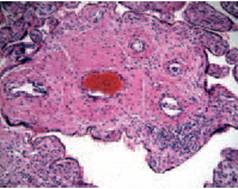

Essa può essere provocata da agenti infettivi provenienti dal circolo materno o da fenomeni autoimmunitari (vedi Foto 3.4).

Foto 3.4 A sinistra villite linfoplasmacellulare multifocale. A destra villite infettiva.